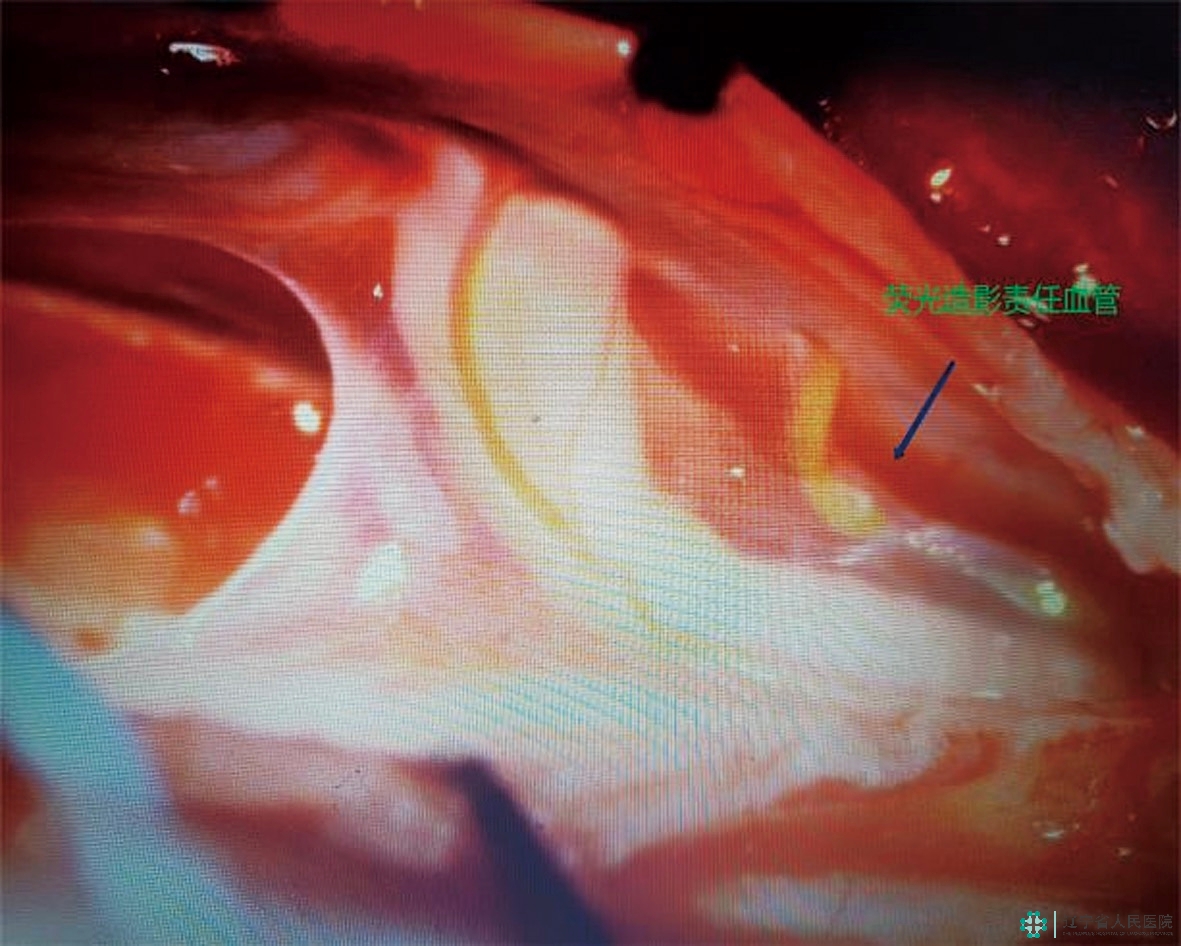

在这一系列环节中,精准定位、寻找瘘口至关重要,也是事关手术成败的最关键一步!臧培卓院长通过ZEISS KINEVO 900机器人手术显微镜独有的FLOW 800彩色荧光技术,使用一种特殊并且安全无毒的材料——吲哚菁绿(ICG),并凭借丰富的术中经验,顺利地确定了病变血管上瘘口的精确位置,为手术成功奠定了坚实基础。接下来,予以电凝后分离静脉、切除瘘口……手术顺利结束。

切断后,再次复查荧光造影,静脉未再显影,瘘口顺利封闭。截至发稿前,刘阿姨的双下肢乏力症状明显改善,已经可以站立行走,实现基本生活自理。